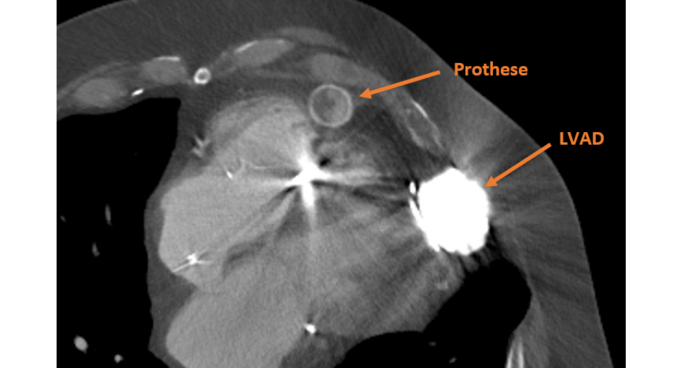

Herzinsuffizienz (Herzschwäche)

Eine Herzinsuffizienz bezeichnet eine verminderte Pumpfunktion des Herzens. Dies wird auch Herzschwäche genannt und entwickelt sich über Jahre hinweg.

Oberarzt der Klinik für Herz-, Thorax- und Gefäßchirurgie, Leiter chirurgische Herzinsuffizienztherapie (z. B. ECLS, LVAD), Strukturelle Herzerkrankungen: TAVI